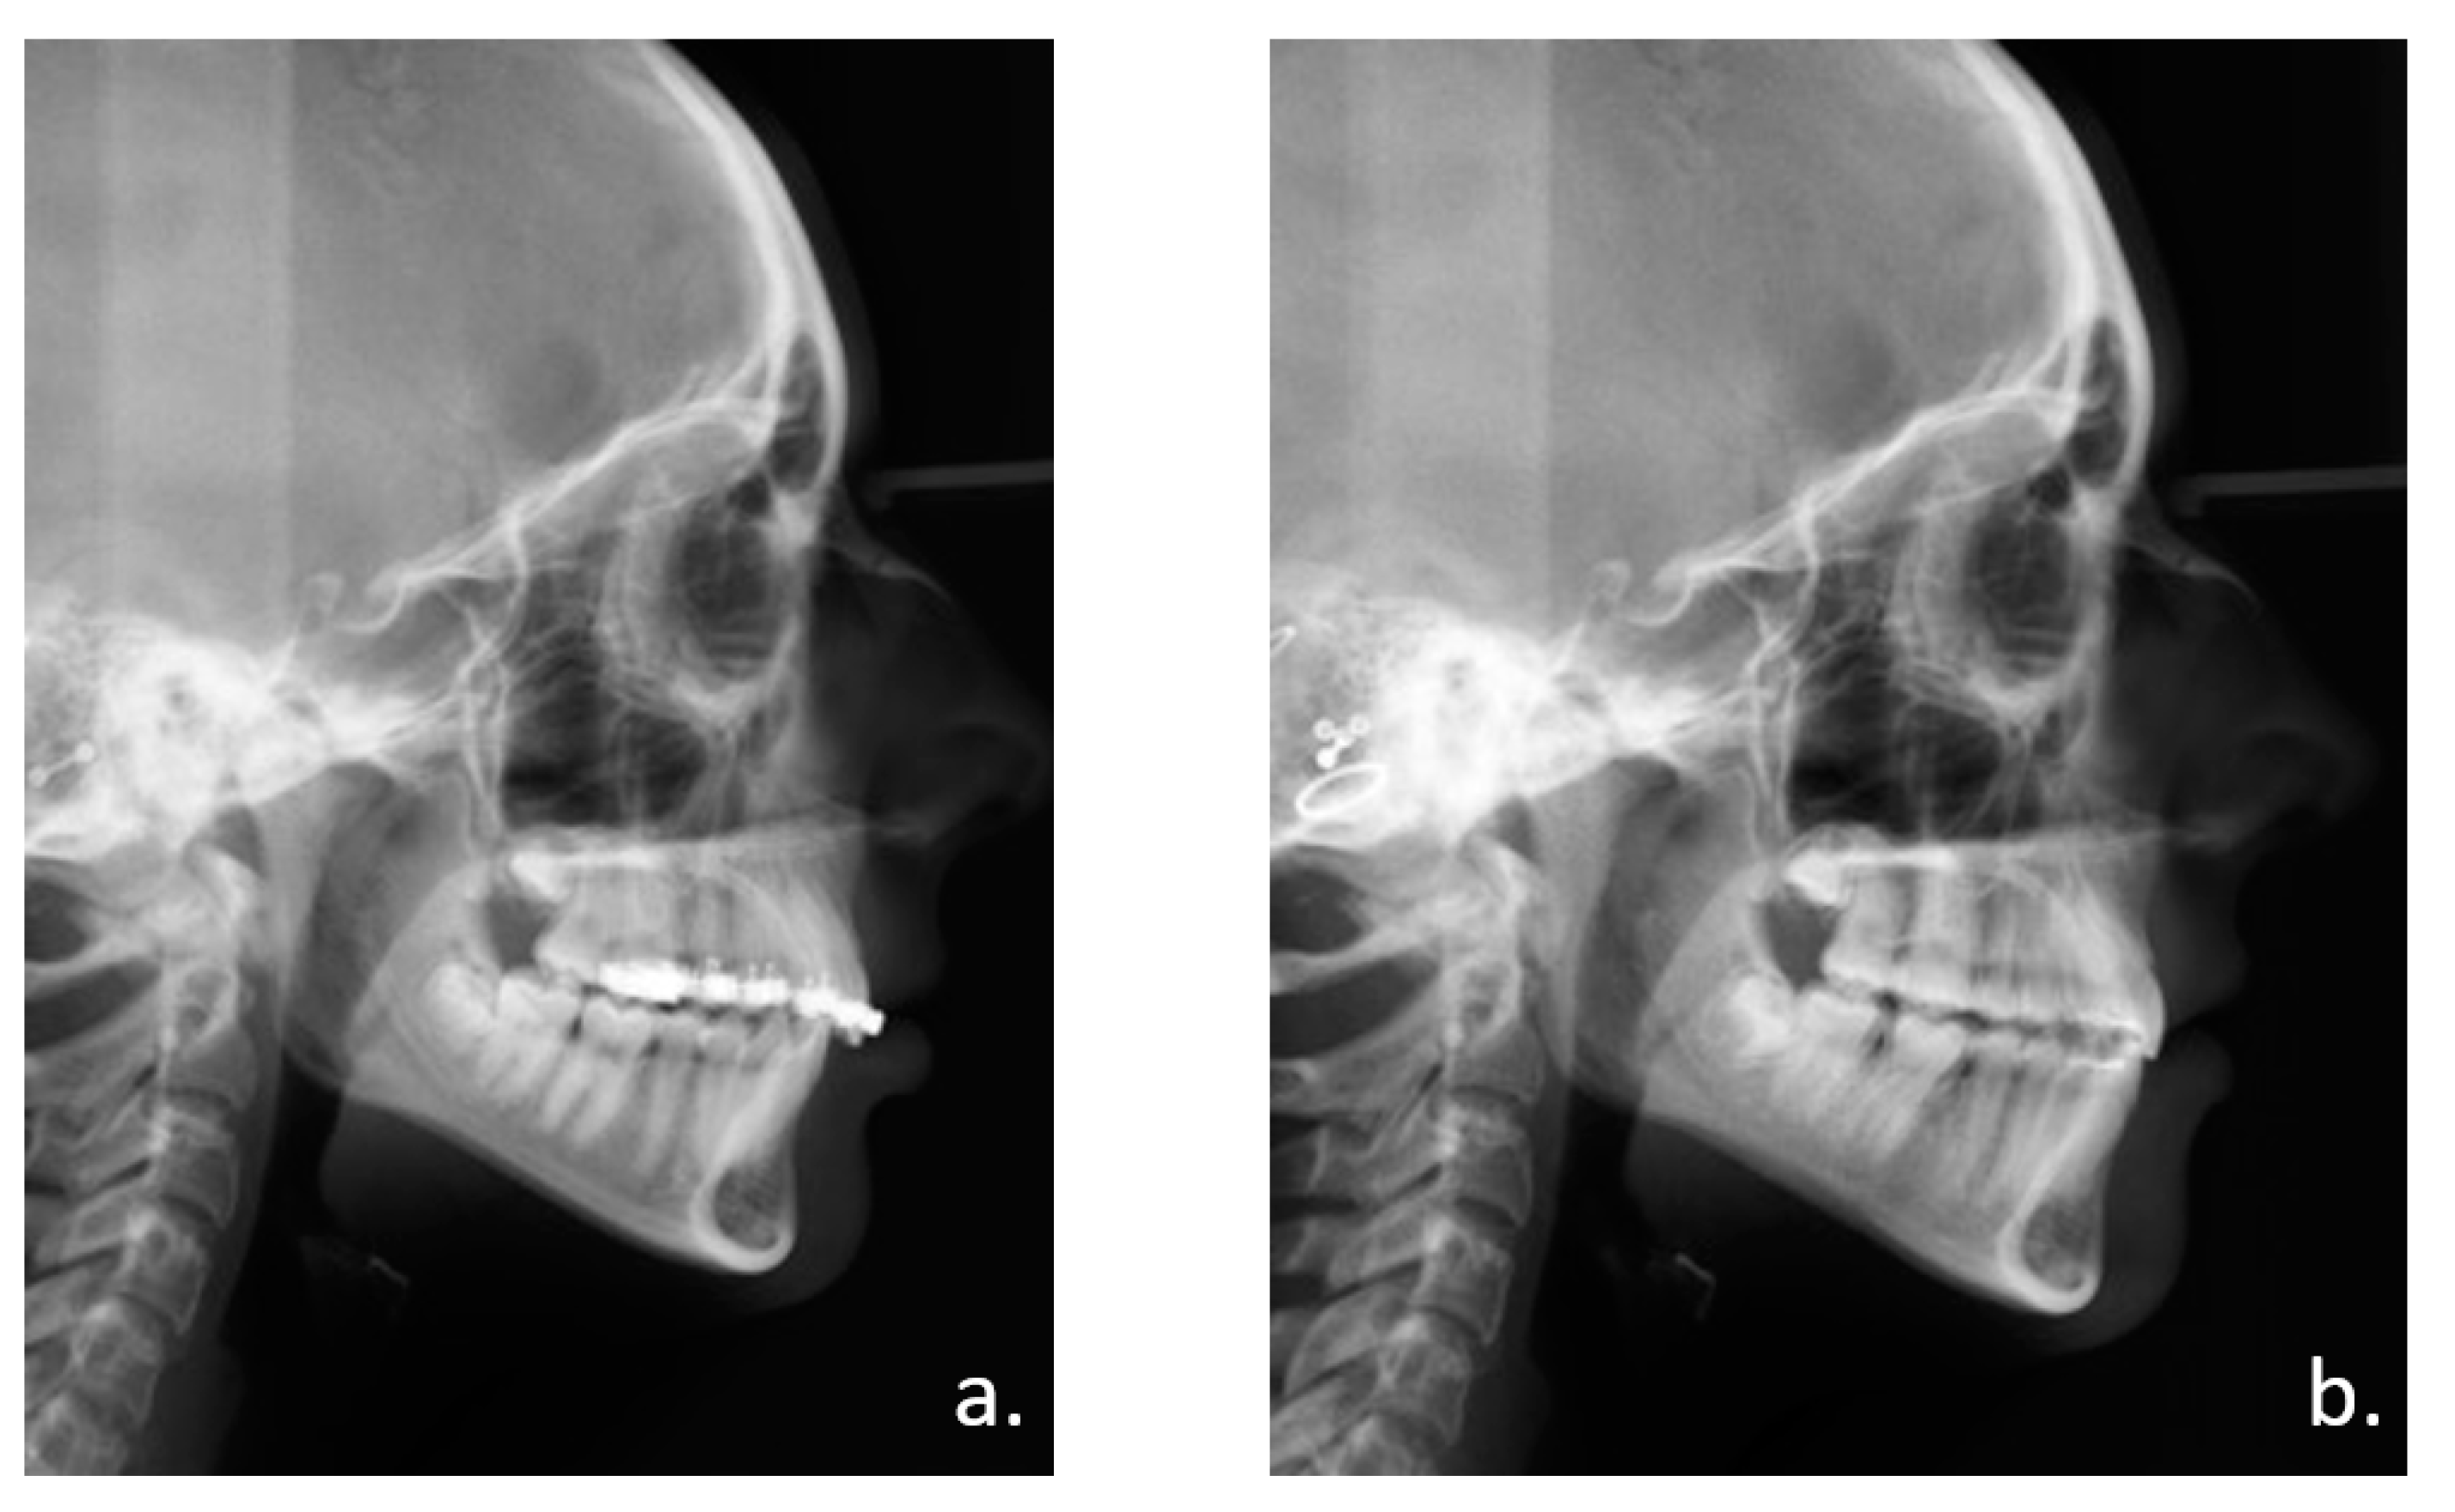

Figure 3.

Radiological follow-up. Panoramic X-rays: (a) Before IMDO. Note the small diastema between the first and second molars of the mandible. (b) Control after distractor placement. Note the symmetrical axis tilt of the distractors. (c) End of active distraction treatment and removal of activation rods for more patient comfort. (d) Bone consolidation 10 weeks after end of distractor activation. (e) After removal of the distractors.

Figure 4.

Lateral skull view (a) before and (b) after treatment with IMDO.